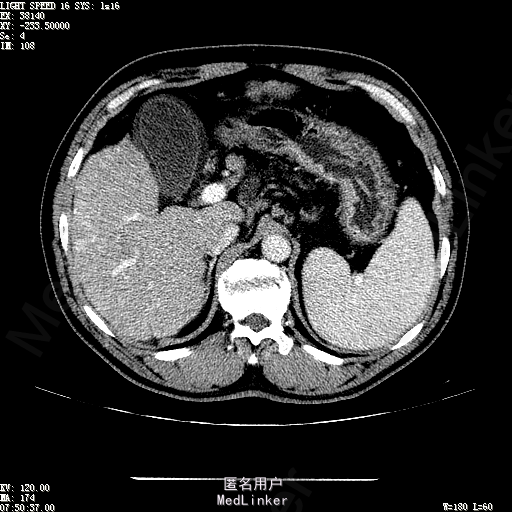

主诉:肝癌TACE治疗后36天 病史:患者两年前体检发现丙型肝炎病毒标志物阳性,于当地医院就诊诊断为"丙肝肝硬化",口服药物治疗,具体用药不详。定期复查肝功及肝脏影像学检查,2月前于医大二院行肝脏增强磁共振检查发现肝S6段动脉期增强结节,36天前在我院行DSA肝动脉造影明确"原发性肝癌"诊断并行"TACE"治疗,术后恢复良好,现患者为进一步行肝癌局部消融治疗来诊。

诊断:1、丙肝肝硬化 代偿期;2、原发性肝癌 S5段、S6段 该患诊断明确,既往曾行TACE治疗肝癌,S5段、S6段近右肾上极2处碘油沉积明确,S5段者较大,约2.31cm。超声显示清晰,为防止癌灶复发,适合行射频消融治疗。